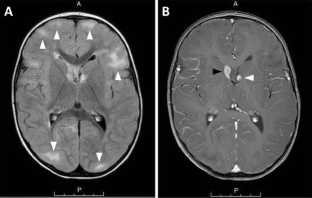

Figure 1